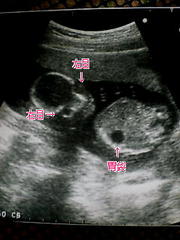

検診

今日は4ヶ月の検診日。 もうお腹の子と過ごして4ヶ月もたったんだぁ。早いね。 半年後には産まれちゃうんだ! だいすけパパ、準備は大丈夫!? ボーロばかり食べて、お昼寝ばっかりしてる場合じゃないよ!! 赤ちゃんは頭から足ま […] 続きを読む »